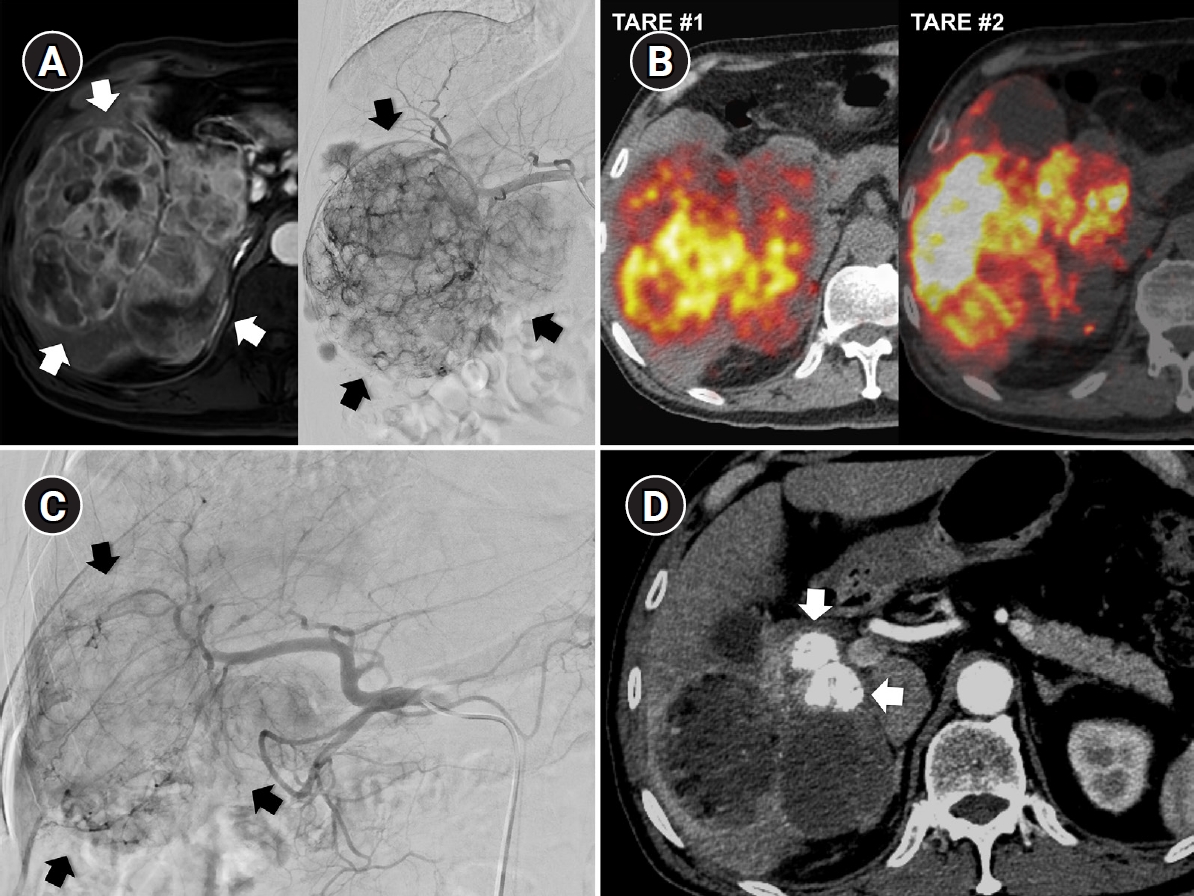

Radiation subsegmentectomy in an 86-year-old man with a single nodular hepatocellular carcinoma. (A) Liver magnetic resonance imaging shows a 2.2-cm hypervascular tumor (arrow) with exophytic growth in segment 6. (B) Hepatic arteriography shows a hypervascular tumor (arrows), and the microcatheter was advanced into a subsegmental branch of A6 (right side image). A total activity of 0.35 GBq of glass microspheres was infused. (C) Post-treatment Y-90 positron emission tomography shows intense uptake at the tumor (arrow), confirming a perfused liver dose of 508.7 Gy and a tumor dose of 1,794.7 Gy. Voxel-based dosimetry showed a D95 of 625 Gy and a V200 of 100% (D95: the minimum dose delivered to 95% of the target volume, V200: the percentage of target volume receiving ≥200 Gy). (D) Twenty-month follow-up computed tomography shows complete response with dystrophic calcification (arrow).

Recent advances in dosimetry optimization have markedly improved the therapeutic outcomes of TARE. Radiation segmentectomy and radiation lobectomy have expanded the role of TARE from a palliative treatment to a potentially curative modality. In early or localized HCC, radiation segmentectomy can achieve complete necrosis by delivering ablative radiation doses confined to one or two hepatic segments (Fig. 1). In the LEGACY study, which included patients with solitary HCCs (median diameter, 2.7 cm; range, 1.0 to 8.1 cm), radiation segmentectomy achieved a 2-year complete response (CR) rate of 84% [12]. In the RASER trial, a single-center prospective study conducted in patients with solitary HCCs ≤ 3 cm, the initial objective response rate was 100 % [18]. This outcome was superior to that reported in a Korean retrospective study (2-year CR rates in 1–10 cm HCCs: 66.2% with conventional TACE and 30.5% with drug-eluting bead TACE [DEB-TACE]) and a Japanese randomized controlled trial (3-month CR rates in 1–5 cm HCCs: 75.2% with conventional TACE and 27.6% with DEB-TACE) [19,20]. Several studies have further demonstrated that radiation segmentectomy can achieve local tumor control rates comparable to those of surgical resection or local ablation, when appropriate dosimetry is achieved [21]. Even for multifocal or bulky tumors, Korean investigators have expanded this principle beyond segmentectomy into a broader concept of radiation “major hepatectomy,” applying ablative doses to larger anatomical territories when disease remains confined and hepatic reserve is adequate (Fig. 2). A Korean study reported a median time to progression of 17.1 months in patients with tumors averaging 11.4 cm in size treated at mean absorbed doses of 418.8 Gy [22]. Radiation lobectomy can also be used when resection is technically feasible but unsafe because the future liver remnant (FLR) is insufficient [23]. By intentionally delivering sufficient radiation dose to non-tumorous parenchyma in the target lobe, contralateral hypertrophy can be induced while simultaneously suppressing tumor progression in the treated lobe [24]. Taken together, these results indicate that territory-based TARE with high radiation dose can serve as a reasonable alternative in patients who are technically resectable but medically inoperable, or in those initially considered for resection who later become unsuitable because of comorbidities or limited hepatic reserve [25].